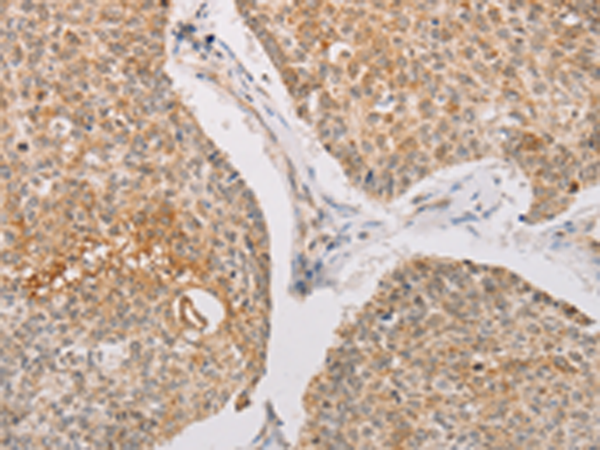

分类: 科研抗体货号: P07972别名: SHIK; SgK495应用: IHC反应种属: Human, Mouse, Rat